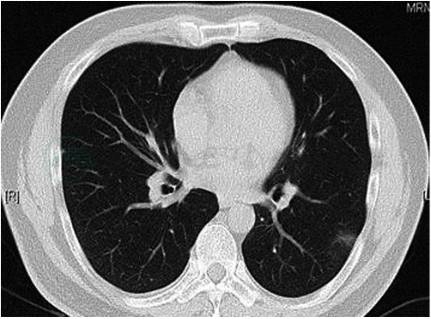

患者口服氟康唑1个月后,复查胸部CT(2018-04-26,图2)示原有病灶大部分吸收。患者症状明显改善。

图2 氟康唑治疗1个月后复查胸部CT示:左肺下叶外侧基底段病灶较前明显吸收